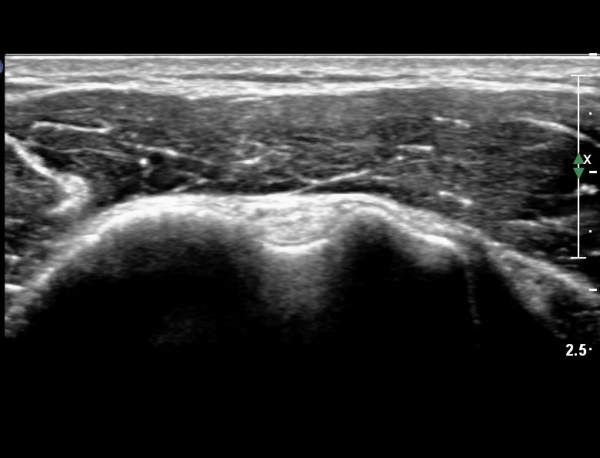

ÀÌµÎ¹Ú±Ù°Ç È¾´Ü¸é°Ë»ç¿¡¼­ °Ç ÁÖÀ§ ¼ö¾×Àú·ù µî ƯÀÌ ¼Ò°ßÀ» º¸ÀÌÁö ¾Ê¾Ò´Ù(»çÁø 1, 2)